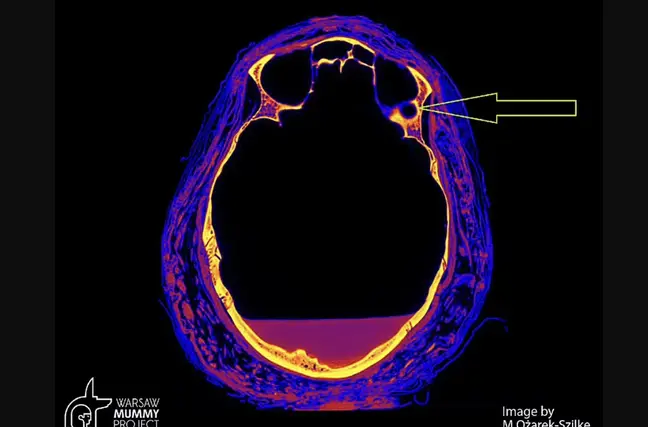

Varşova Mumya Projesi'nden alınan mumya tarama görüntüleri, kafatasında büyük olasılıkla bir tümörün neden olduğu lezyonları ve ayrıca mumyalamada tipik olarak bulunmayan kemik kısımlarındaki çeşitli kusurları gözler önüne serdi.

Varşova Tıp Üniversitesi Onkoloji Bölümü'nden Profesör Rafał Stec mumya araştırması hakkında şunları söyledi: “Nazofaringeal kemiklerde, mumya uzmanlarına göre mumyalama sürecinin tipik olmayan olağandışı komplikasyonlar var. İkinci olarak bilgisayarlı tomografiye dayalı radyoloji görüntüleri, kemiklerde tümör değişikliği oranını gösteriyor.